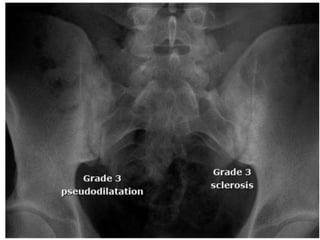

• The SI joint abnormalities are typically graded

to identify the nature and severity of

• Grade 3: unequivocal abnormality – moderate

or advanced sacroilitis with one or more of

the following: erosions, sclerosis, joint space

widening, narrowing, or partial ankylosis.

• The SIjoint abnormalities are typically graded to identify the nature and severity of involvement. • Grade 0 : Normal. • Grade 1: Suspicious(but not definite) changes • Grade 2: minimal abnormality- small areas of erosions or sclerosis without alteration of joint width.

• Grade 3:unequivocal abnormality – moderate or advanced sacroilitis with one or more of the following: erosions, sclerosis, joint space widening, narrowing, or partial ankylosis. • Grade 4: total ankylosis of joints